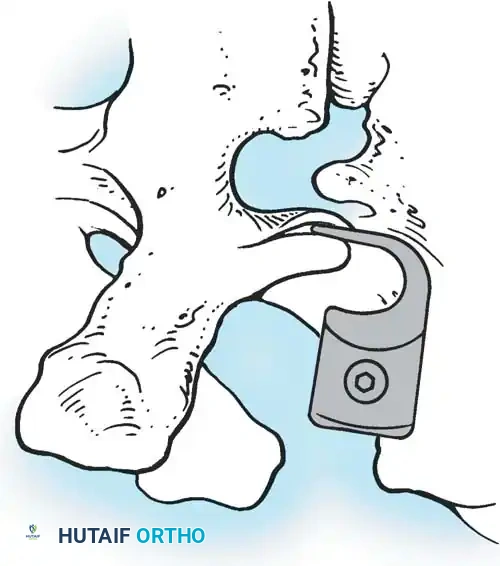

The Hall Technique

The Hall technique offers an alternative method for facet obliteration and grafting, particularly useful in rigid deformities.

Fig. 38-28: The Hall technique of facet fusion, involving sharp excision of the inferior facet and trough creation.

- Sharply amputate the inferior articular facet with a gouge and remove the bone fragment entirely. This exposes the cartilage of the superior facet.

- Remove the exposed cartilage completely with a sharp curet.

- Create a bleeding trough by removing the outer cortex of the superior facet.

- Impact cancellous bone grafts directly into this vascularized trough.

- Complete the procedure with global decortication of the posterior elements.